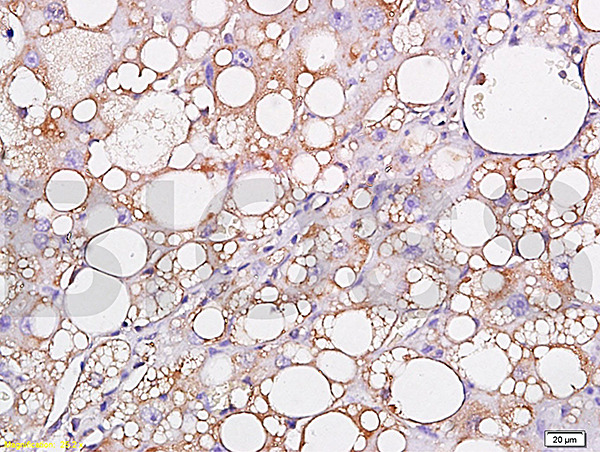

- Main image

- Experimental details

- Formalin-fixed and paraffin embedded: rat liver labeled with Anti-Leptin Polyclonal Antibody (bs-0108R), Unconjugated 1:300 followed by conjugation to the secondary antibody and DAB staining

- Sample type

- Rat

- Other comments

- Liver